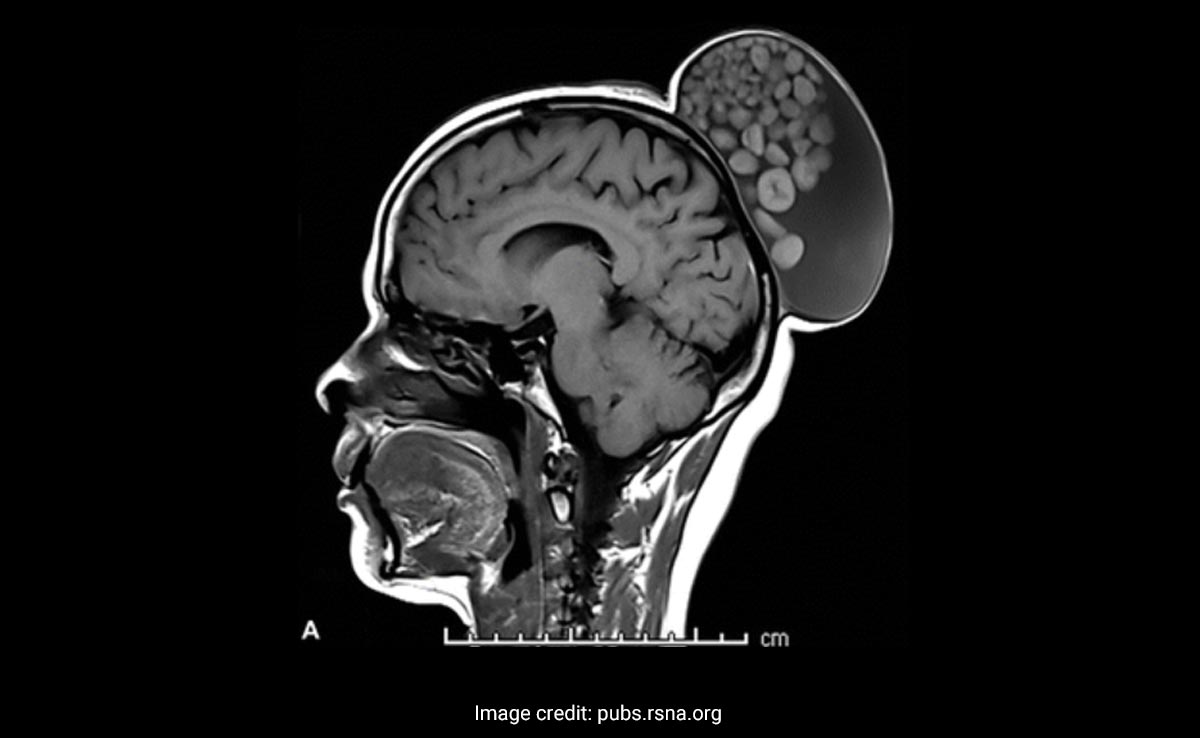

An MRI scan showed the cyst on the back of the woman's head like a fleshy hair bun. Upon removing the growth, the medics noticed that the lesion was filled with fluid, hair, and fatty molecules with "thick outer rims", and balls of keratin of varying sizes.